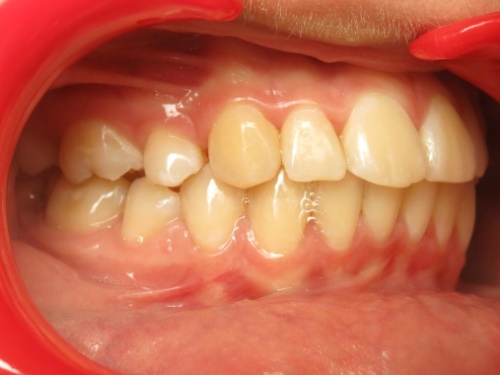

1 - Arcades dentaires avant-après

Les photos montrent un encombrement dentaire important associé à une classe II dentaire. Les extractions de prémolaires ont été décidées non seulement pour créer la place nécessaire à l’alignement, mais aussi pour corriger le décalage de classe II. Le résultat final illustre qu’un plan de traitement bien réfléchi peut répondre simultanément aux impératifs fonctionnels et esthétiques, sans compromettre l’harmonie faciale.

Le recul progressif des dents encombrées dans les espaces d’extraction créés à cet effet a été rendu possible grâce à l’utilisation de brackets autoligaturants, particulièrement efficaces pour respecter l’angulation et le torque des dents. Tous les espaces d’extraction ont été exploités pour résoudre l’encombrement, évitant ainsi tout recul des dents antérieures. L’occlusion obtenue est physiologique, en classe I canine et en classe II molaire thérapeutique.